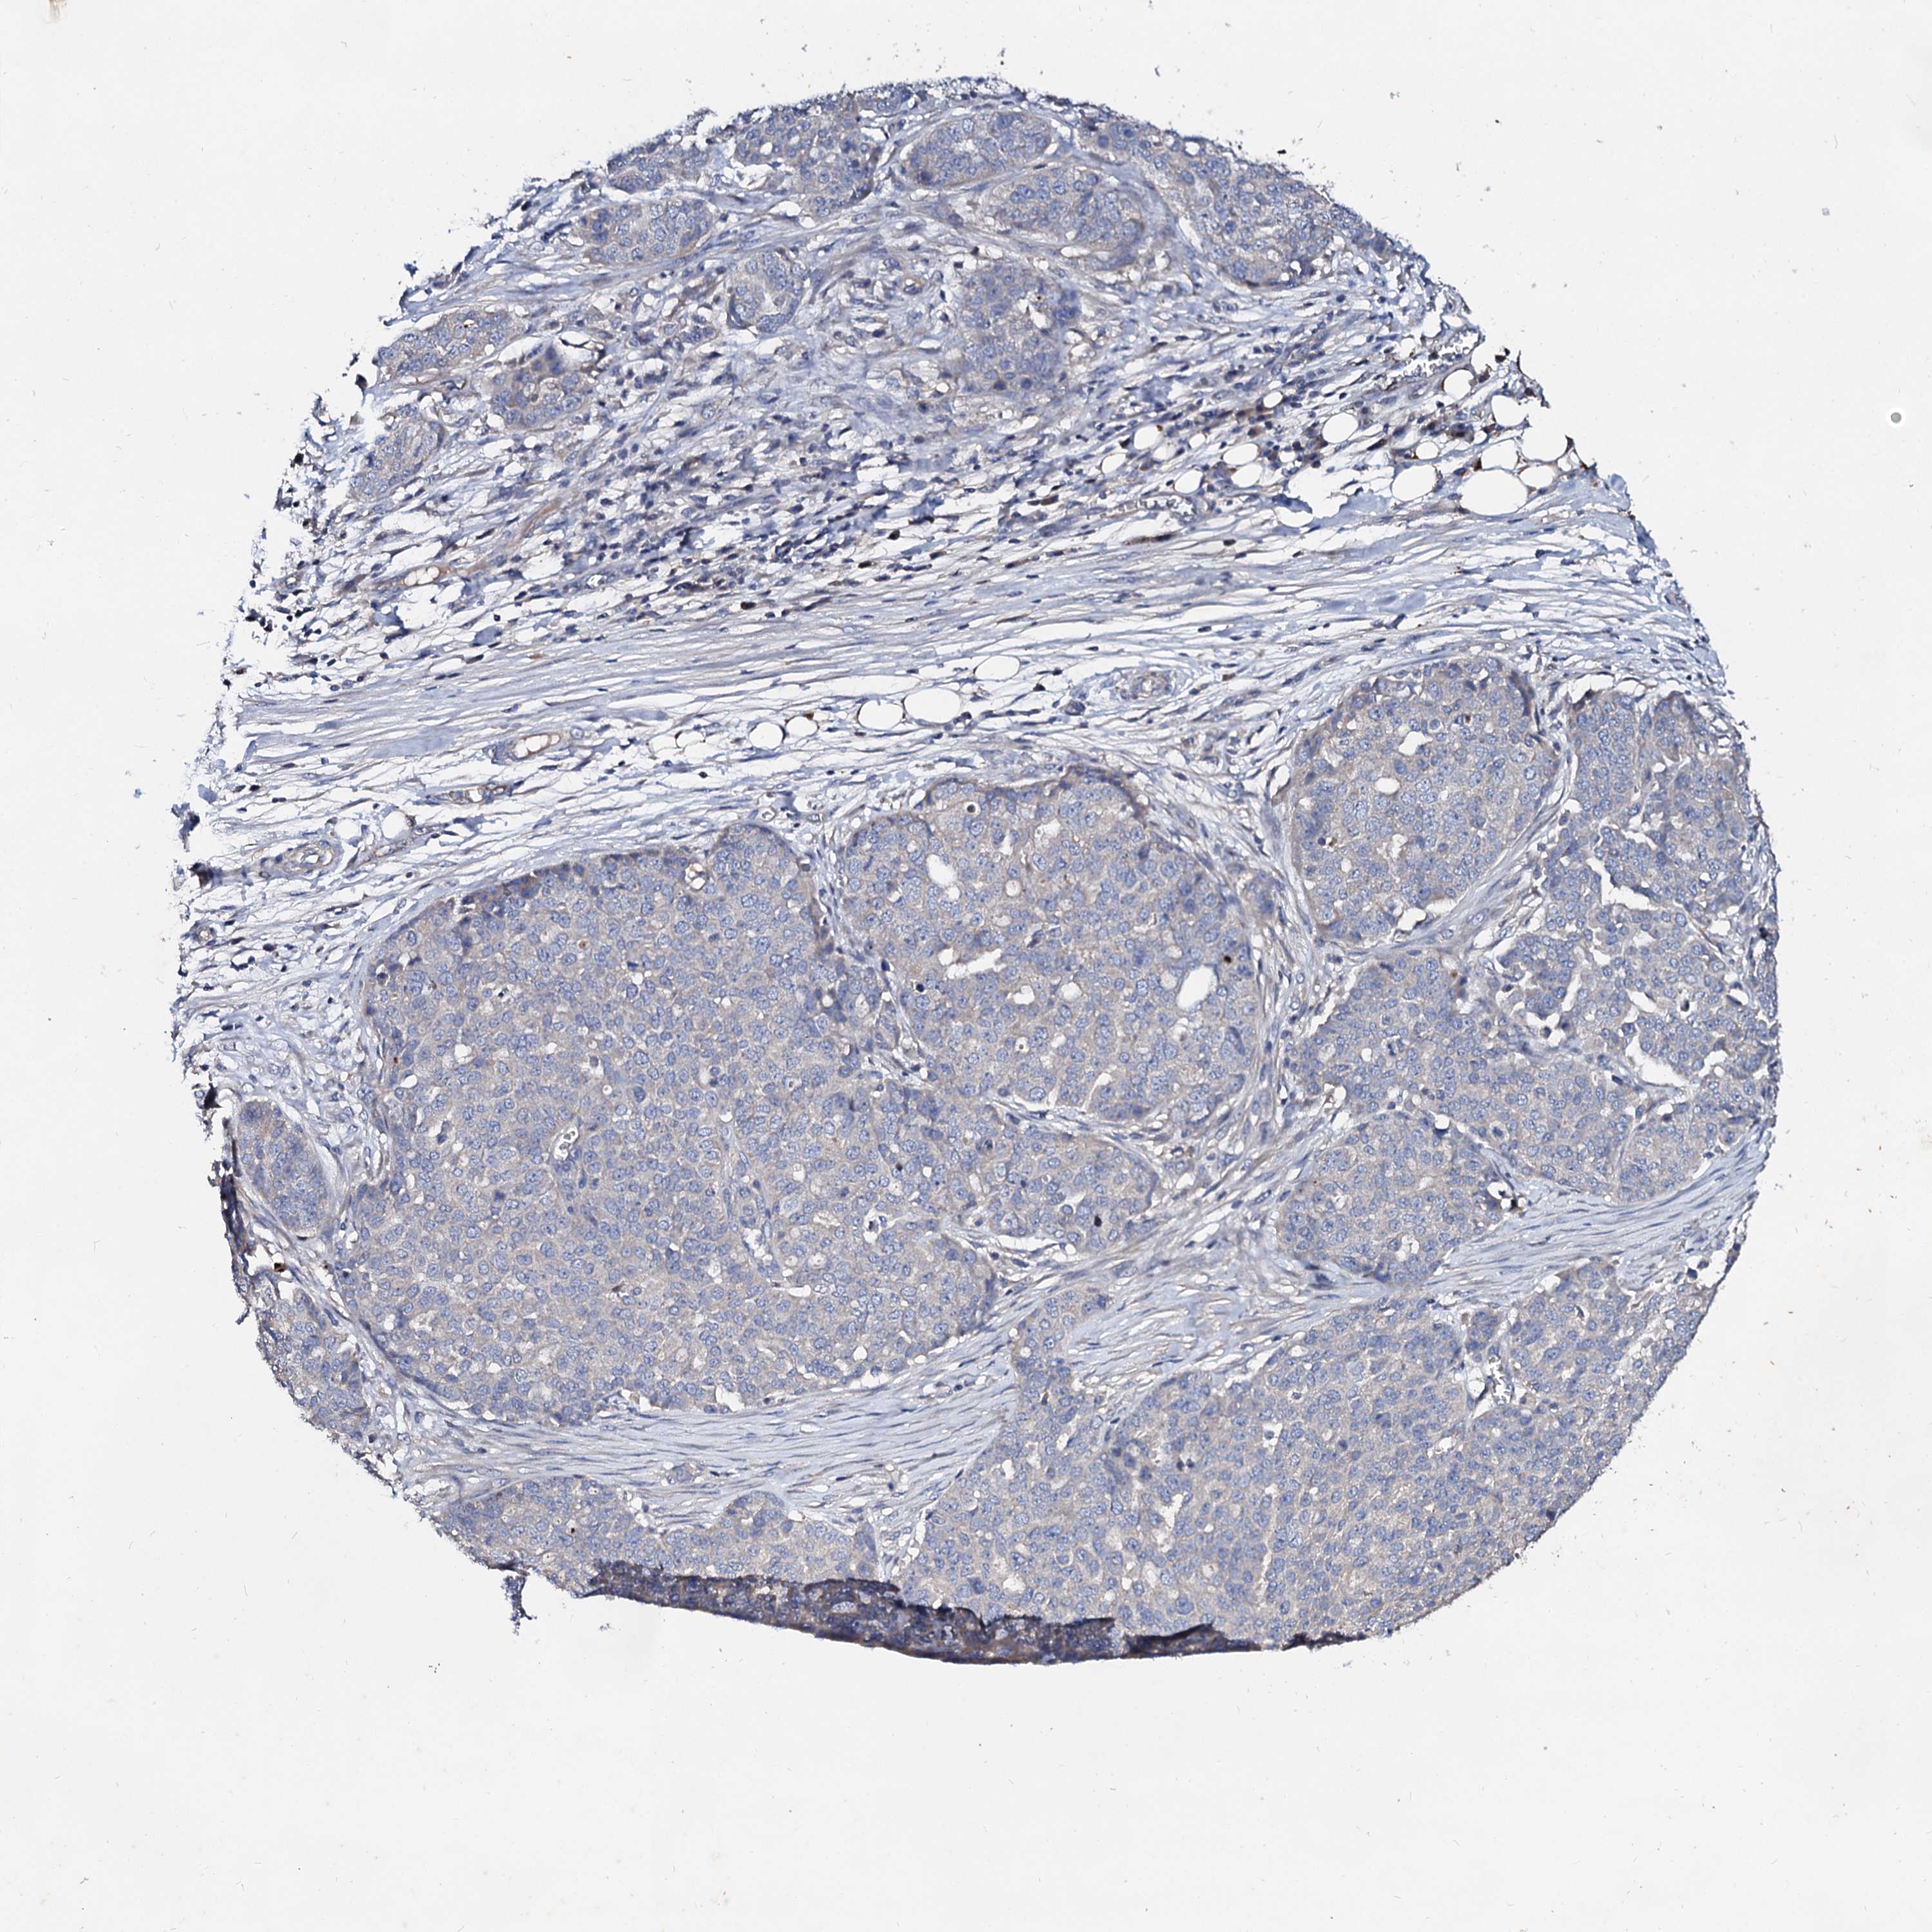

OVARIAN CANCER - Protein expressioni

A mouse-over function shows sample information and annotation data. Click on an image to view it in a full screen mode. Samples can be filtered based on level of antibody staining by selecting one or several of the following categories: high, medium, low and not detected. The assay and annotation is described here.

Note that samples used for immunohistochemistry by the Human Protein Atlas do not correspond to samples in the TCGA dataset.

Antibody stainingi

Antibody staining in the annotated cell types in the current human tissue is reported as not detected, low, medium, or high, based on conventional immunohistochemistry profiling in selected tissues. This score is based on the combination of the staining intensity and fraction of stained cells.

Each image is clickable and will lead to virtual microscopy that enables deeper exploration of all samples and also displays staining intensity scores, fraction scores and subcellular localization as well as patient and tissue information for each sample.

Antibody HPA040120

Staining

High

Medium

Low

Not detected

Intensity

Strong

Moderate

Weak

Negative

Quantity

>75%

75%-25%

<25%

None

Location

Nuclear

Cytoplasmic/membranous

Cytoplasmic/membranous,nuclear

Cystadenocarcinoma, serous, NOS

Carcinoma, endometroid

Cystadenocarcinoma, mucinous, NOS

Carcinoma, NOS